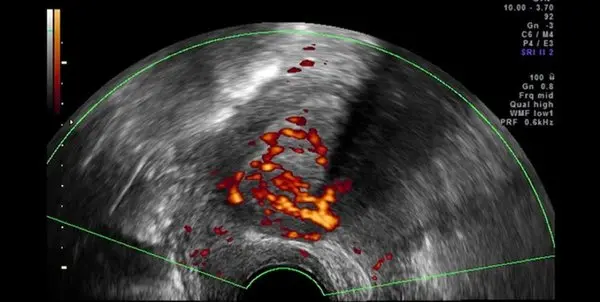

رکنا: رئیس کنگره بینالمللی چالشهای بالینی با اشاره به شیوع بیماری آندومتریوز در میان زنان، گفت: درمانهای دارویی ،لاپاراسکوپی و جراحیهای باز از جمله روشهای درمان این بیماری است.

حسینی خاطرنشان کرد: انجام لاپاراسکوپی، جراحیهای باز و درمان دارویی از جمله روشهای درمانی بیماران مبتلا به آندومتریوز به شمار میرود و باید توجه داشت که درمان دارویی عمدتاً به این جهت بوده که فاصله بین زمانهای قاعدگی را بیشتر کند تا از این طریق علاوه بر جلوگیری از پیشرفت آندومتریوزیس، درد آنها نیز کاهش دهد.